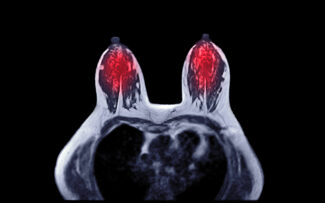

The purpose of this month is not only to encourage regular screening but also to educate women about their personal risk factors, warning signs, and available diagnostic imaging. Greater Waterbury Imaging Center (GWIC) supports this effort through comprehensive breast imaging services, including MRI breast imaging and MRI-guided biopsy, which help physicians detect abnormalities earlier.

- Breast MRI provides greater sensitivity, especially for high-risk individuals or those with dense breast tissue.

- Breast MRI: Provides high-resolution, multiplanar imaging for high-risk patients or when mammogram or ultrasound results are inconclusive.